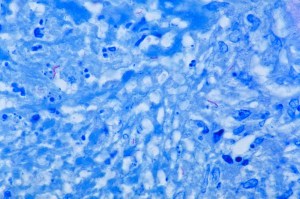

According to the World Health Organization, developing-world diseases like HIV/AIDS, malaria, tuberculosis, and NTDs affect over 1 billion people, yet there is a striking lack of attention devoted to such maladies. This is, in large part, due to the lack of financial incentives for pharmaceutical companies to research and create effective drugs. Even developed drugs are often shelved while companies shift their focus to high-demand products that garner greater fiduciary rewards. The biggest obstacle to progress in combating infectious disease isn’t a lack of technology or knowledge; rather, it is a misdirected focus.

The GHIT began by funding and facilitating the TB Alliance, MMV (Medicines for Malaria Venture), and DNDi (Drugs for Neglected Diseases Initiative). Through GHIT support, these product development partnerships have access to Japanese pharmaceutical compound libraries and the financial resources to develop potentially effectual drugs.

At the 5th Tokyo International Conference on African Development, the GHIT Fund announced thirteen groundbreaking agreements: the TB Alliance will develop compounds against drug resistant TB strains, the MMV will seek new treatments that bypass similar obstacles, and the DNDi will find treatments for leishmaniasis, Chagas disease, and sleeping sickness.